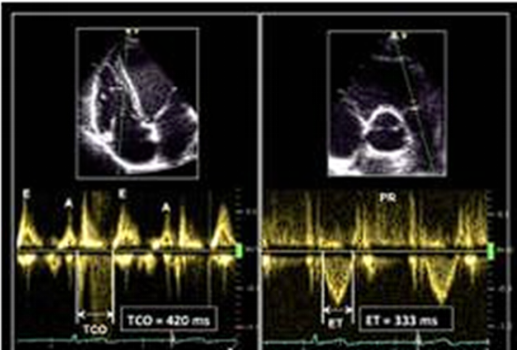

(4)右心室Tei指数(RV MPI):即为多普勒心肌工作指数,选择脉冲多普勒技术(PW),在右室流入道和流出道取样,并连接心电图以获得相应的数据。或根据三尖瓣环组织多普勒(TDI)测定三尖瓣关闭-开放时间(TCO),TCO=等容收缩期(IVCT)+射血时间(ET)+等容舒张期(IVRT)。

RV MPI=[等容收缩时间(IVCT)+等容舒张时间(IVRT)]/射血时间(ET),但实践中常规规定RV MPI=[三尖瓣反流时间(TCO)-右室流出道射血时间(ET)]/右室流出道射血时间(ET)。RV MPI的PW测量大于0.4或TDI测量大于0.55一般认为右心心肌功能的恶化。

图片

图17. RV MIP的测量

注:上图为PW测量,RV MIP=(TCO-ET)/ET,图为TDI测量,(IVRT+IVCT)/ET